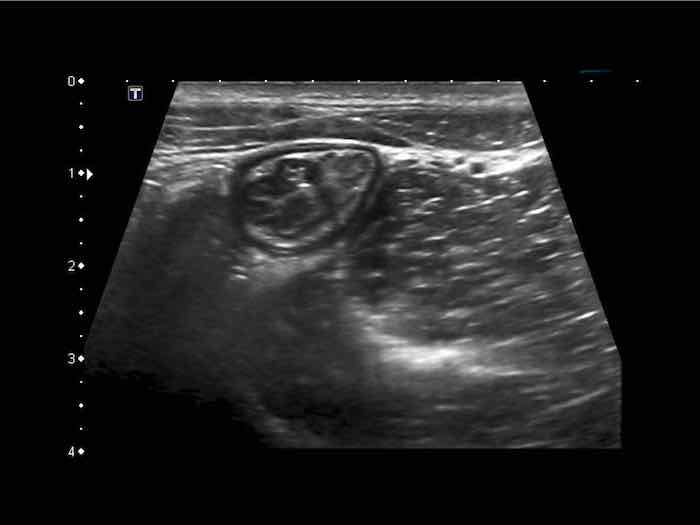

Hình ảnh siêu âm kinh điển của lồng ruột hồi-manh tràng ở hai trẻ khác nhau.

Trong cả hai trường hợp, đoạn hồi tràng bị lồng được định vị không đối xứng bên trong ống lồng ngoài, do mạc treo ruột tăng âm có chứa mỡ, bám vào hồi tràng và đi theo hồi tràng khi bị kéo vào trong.

Trong mạc treo, siêu âm cho thấy một hạch bạch huyết mạc treo (hbh) phóng đại ở cả hai.

Các hạch này phì đại như một phần của tình trạng tăng sản hạch bạch huyết toàn thân và khônghu trú trong lòng hồi tràng.

Do đó đây không phải là điểm dẫn đầu nguyên phát. Ở bệnh nhân bên phải, ruột thừa (mũi tên) cũng bị kéo vào trong.

Lưu ý cấu trúc đa lớp của thành bụng phía trước của phức hợp lồng ruột, đại diện cho ba lớp thành ruột bị gấp lại.